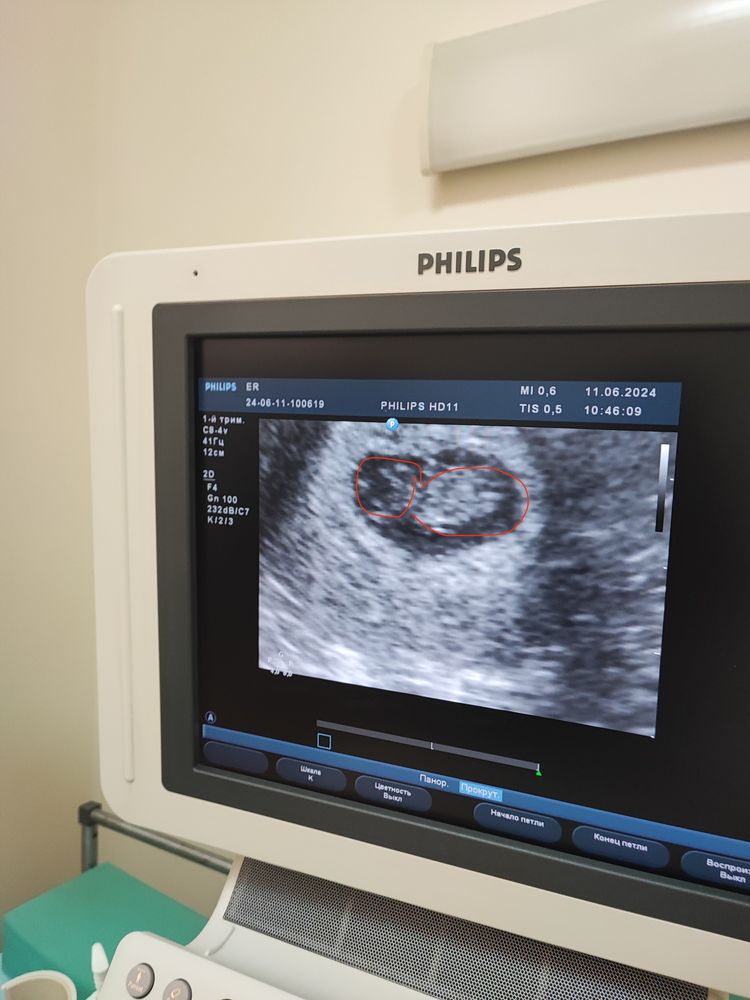

Неделю назад КТР 1,5, СДПЯ 2.1, ЧСС 140 деформация из за гипертонуса, срок по УЗИ 8 недель, Сегодня КТР 1,95 СДПЯ 2.2 деформации нет, тонуса нет. ЧСС 175, срок по УЗИ 8 недель 5 дней.

Ирина, просто СДПЯ 2.2 а в прошлый раз было 2.1, но в прошлый раз была деформация из за тонуса, ПЯ вообще было вытянутое, а сегодня круглое